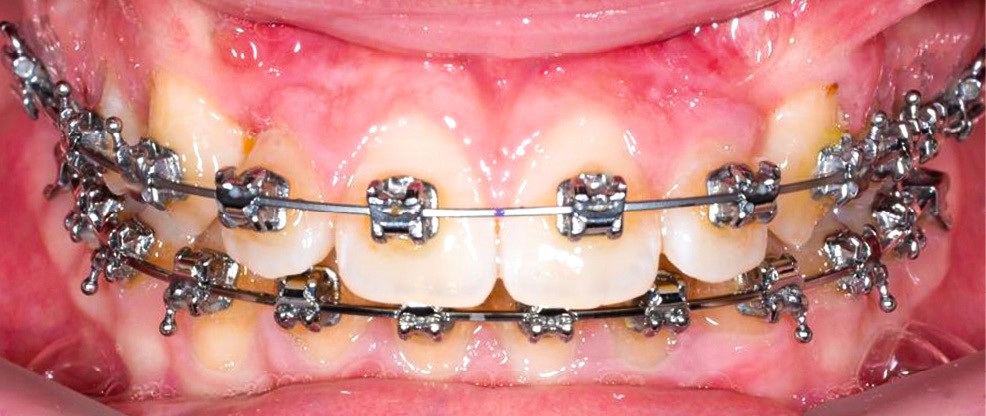

Un appareil multi-attache est mis en place avec une prescription MBT en .022 x .028. une fois les faces vestibulaires des canines maxillaires apparentes. 13 et 23 ne sont pas prises en charge dans l’arc pour éviter les effets parasites sur les dents adjacentes. Leur traction est poursuivie avec des élastiques de Classe II (1/4” – 3.5 oz) en port nocturne. Ces élastiques sont portés sur un bouton palatin pour la 23 afin de corriger sa rotation mésio-vestibulaire. Une fois les canines suffisamment proches du plan occlusal, elles sont prises en charge dans un arc continu en suivant les séquences suivantes : .014, .018 et .019 x .025 Niti. Une fois l’arc .019 x .025 en Niti en place pendant huit semaines, l’arc transpalatin est déposé. L’arcade mandibulaire suit cette même séquence d’arcs avec l’ajout d’un arc en acier .019 x .025 avec courbe de Spee inversée pour aider à la correction de la supraclusion.

Un arc acier .019 x .025 est inséré à l’arcade maxillaire et les finitions sont réalisées sur des arcs en TMA .017 x .025.

L’appareil est déposé après la mise en place de contentions collées de 12 à 22 et de 33 à 43 avec le port nocturne d’une plaque de Hawley à l’arcade maxillaire. Le temps de traitement actif a été de 41 mois.